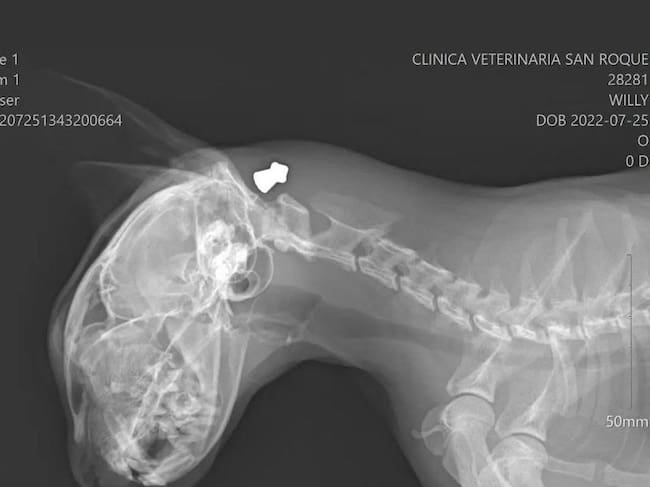

La Guardia Civil de Crevillent está buscando al responsable de disparar en el cráneo a un gato en la pedanía de El Realengo, en Crevillent. Los hechos ocurrieron el pasado domingo cuando los dueños de Willy llegaron a casa y encontraron al gato sangrando por la cabeza donde le observaron un orificio. De inmediato acudieron al veterinario que en su informe describe una herida en la base de la oreja izquierda y un bulto en el cuello. En las radiografías se observa, según el experto, un enfisema subcutáneo con un elemento metálico de menos de un centímetro. Se trataba de un perdigón de un rifle de aire comprimido que por milímetros no acabó con la vida del pequeño animal.

Radiografía de Willy